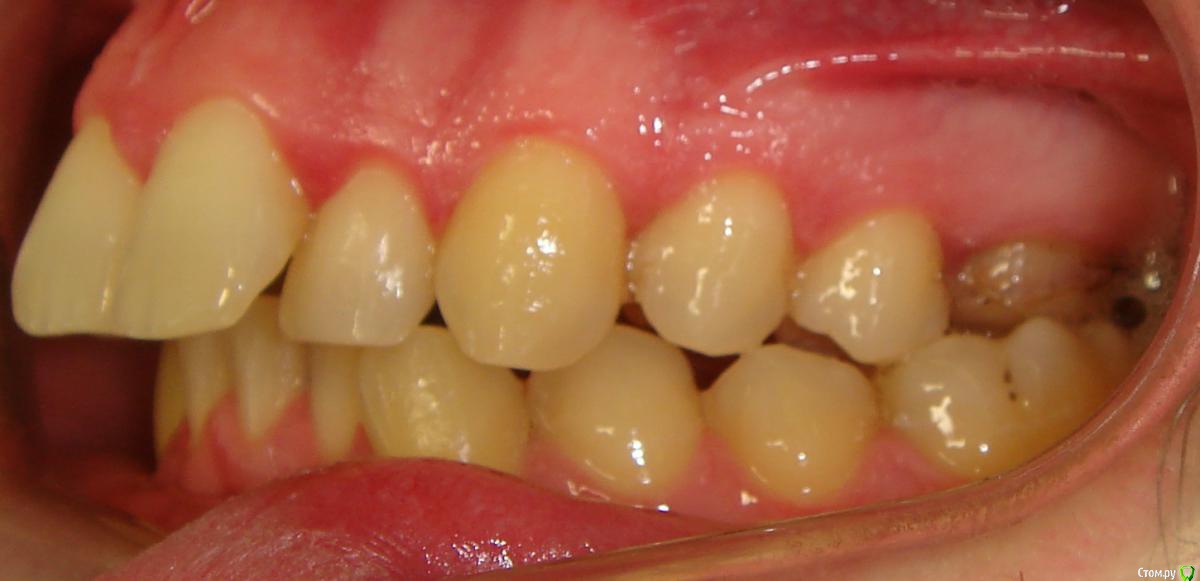

Здравствуйте, Коллеги. Вот такой вот случай, пациент 32 года. Изначально, хотел дистализировать в первом сегменте с целью апрайтинга 13 - 16, провести апрайтинг боковых зубов н/ч, затем САРПЕ и MEAW, понятно, что восьмерки долой еще до лечения. Но потом увидел форму корней 37, 47 (это не искажение, по КТ они и правда такие) и кисты прорезывания за ними. В связи с этим мне кажется, что апрайтинг снизу невозможен, так как эти верхушки никуда меня не пустят, разве что ввиду проблем с пародонтом семерки тоже уйдут. Вопрос: что делать??? Даже если отбросить мультилуп и готовить его на ортогнатию, то апрайт все-равно нужен, как поступить? Заранее спасибо!

P.S.: Забыл... сверху семерки такие же.